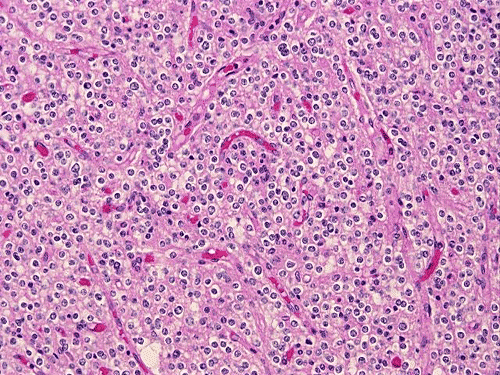

Panel A and B are low-magnification photomicrographs featuring solid sheets of isomorphous, small round to ovoid neoplastic cells with a delicate but rich vascular network. There are also intervening irregular patches of fibrillary neuropils. At high-magnification, the tumor cells appear as fairly uniform round to polygonal cells with perinuclear halo (Panel C). An island of neuropil is present in Panel D. The tumor cells are immunoreactive for synaptophysin (Panel E). The tumor cells were not immunoreactive for neurofilament proteins. At the ultrastructural level, the neoplastic cells contain numerous cell processes filled with vessicles and dense core granules (Panel F and G). Dense core granules and vescicles in high-mangification are shown in Panel H. The vesicles have structures similar to that of the synaptic vesicles, a feature of neuronal differentiation.

Histological, the tumor is composed of solid sheets of small, round to polygonal, isomorphic tumor cells with distinct cell membrane. Within the neoplastic cells is a delicate vascular network. Microcalcifications, when present, are distributed throughout the tumor. The cytoplasm is fine and amphophilic. Perinuclear halo is usually present and prominent, leading to an impression of a clear cell tumor. The summation of these features generates a “honey-comb” pattern similar to that of oligodendroglioma and clear cell ependymoma. The nuclei of neurocytoma are round, small, and contain fine and speckled chromatin. Nucleoli are indistinct. Mitotic figures are not readily seen or infrequent. Irregular and small islands of neuropils are present. Perivascular arrangement of neuropils in some areas may closely mimic the coronary perivascular fibrillary hypocellular mantles (perivascular pseudorosettes) that are considered evidence of ependymoma. The real ependymal pseudorosettes are more orderly and fibrillary. A high index of suspicion is important to avoid this trap.